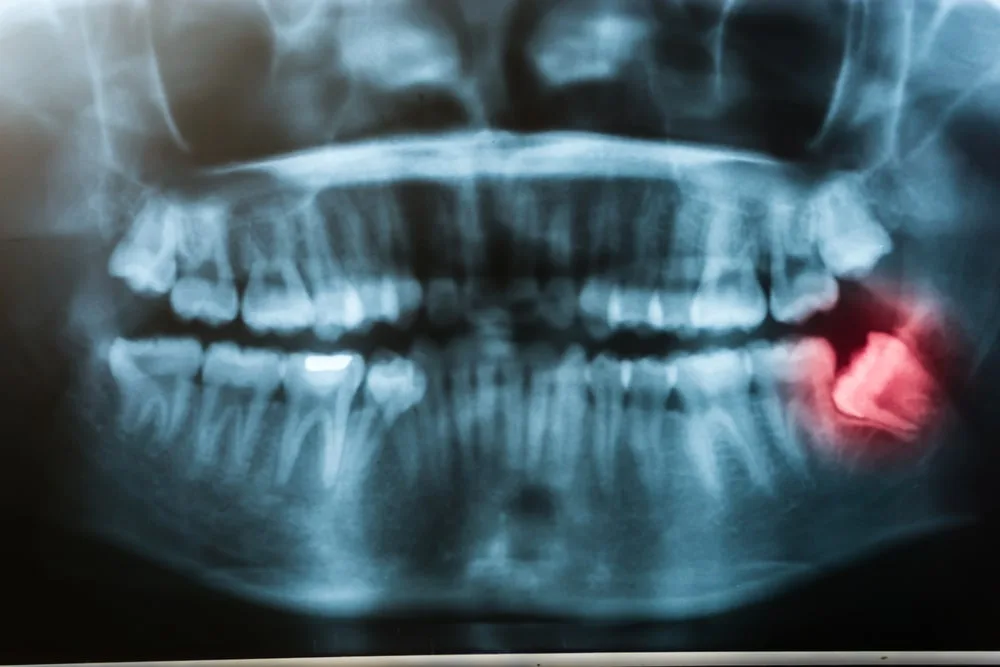

Tooth extraction may be recommended to improve your oral health. For example, cases that include impaction, periodontal disease, and severe tooth infection may result in tooth extraction. Wisdom teeth are commonly removed in such situations due to the high risk of overcrowding and future dental issues. Furthermore, extracting a tooth is performed by our dentists. It may be a simple tooth pulling or involve a surgical approach. This depends on the tooth’s placement. However, your exam and consultation will offer more insight. Nonetheless, learn more about tooth extraction below.